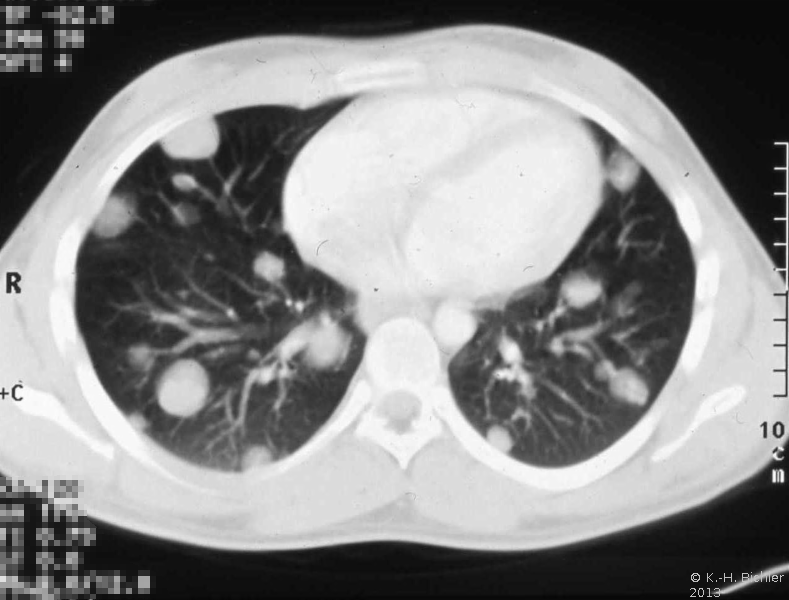

Die Sonographie zeigt einen abgegrenzten, inhomogenen, z.T. auch den ganzen Hoden einnehmenden Tumor. Kalzifizierungen äußern sich in Schlagschattenbildungen (s. Abbildung 3a). CT von Abdomen und Thorax sind zur Erfassung von Lymphknoten- bzw. Lungenmetastasen erforderlich (Abbildung 2).